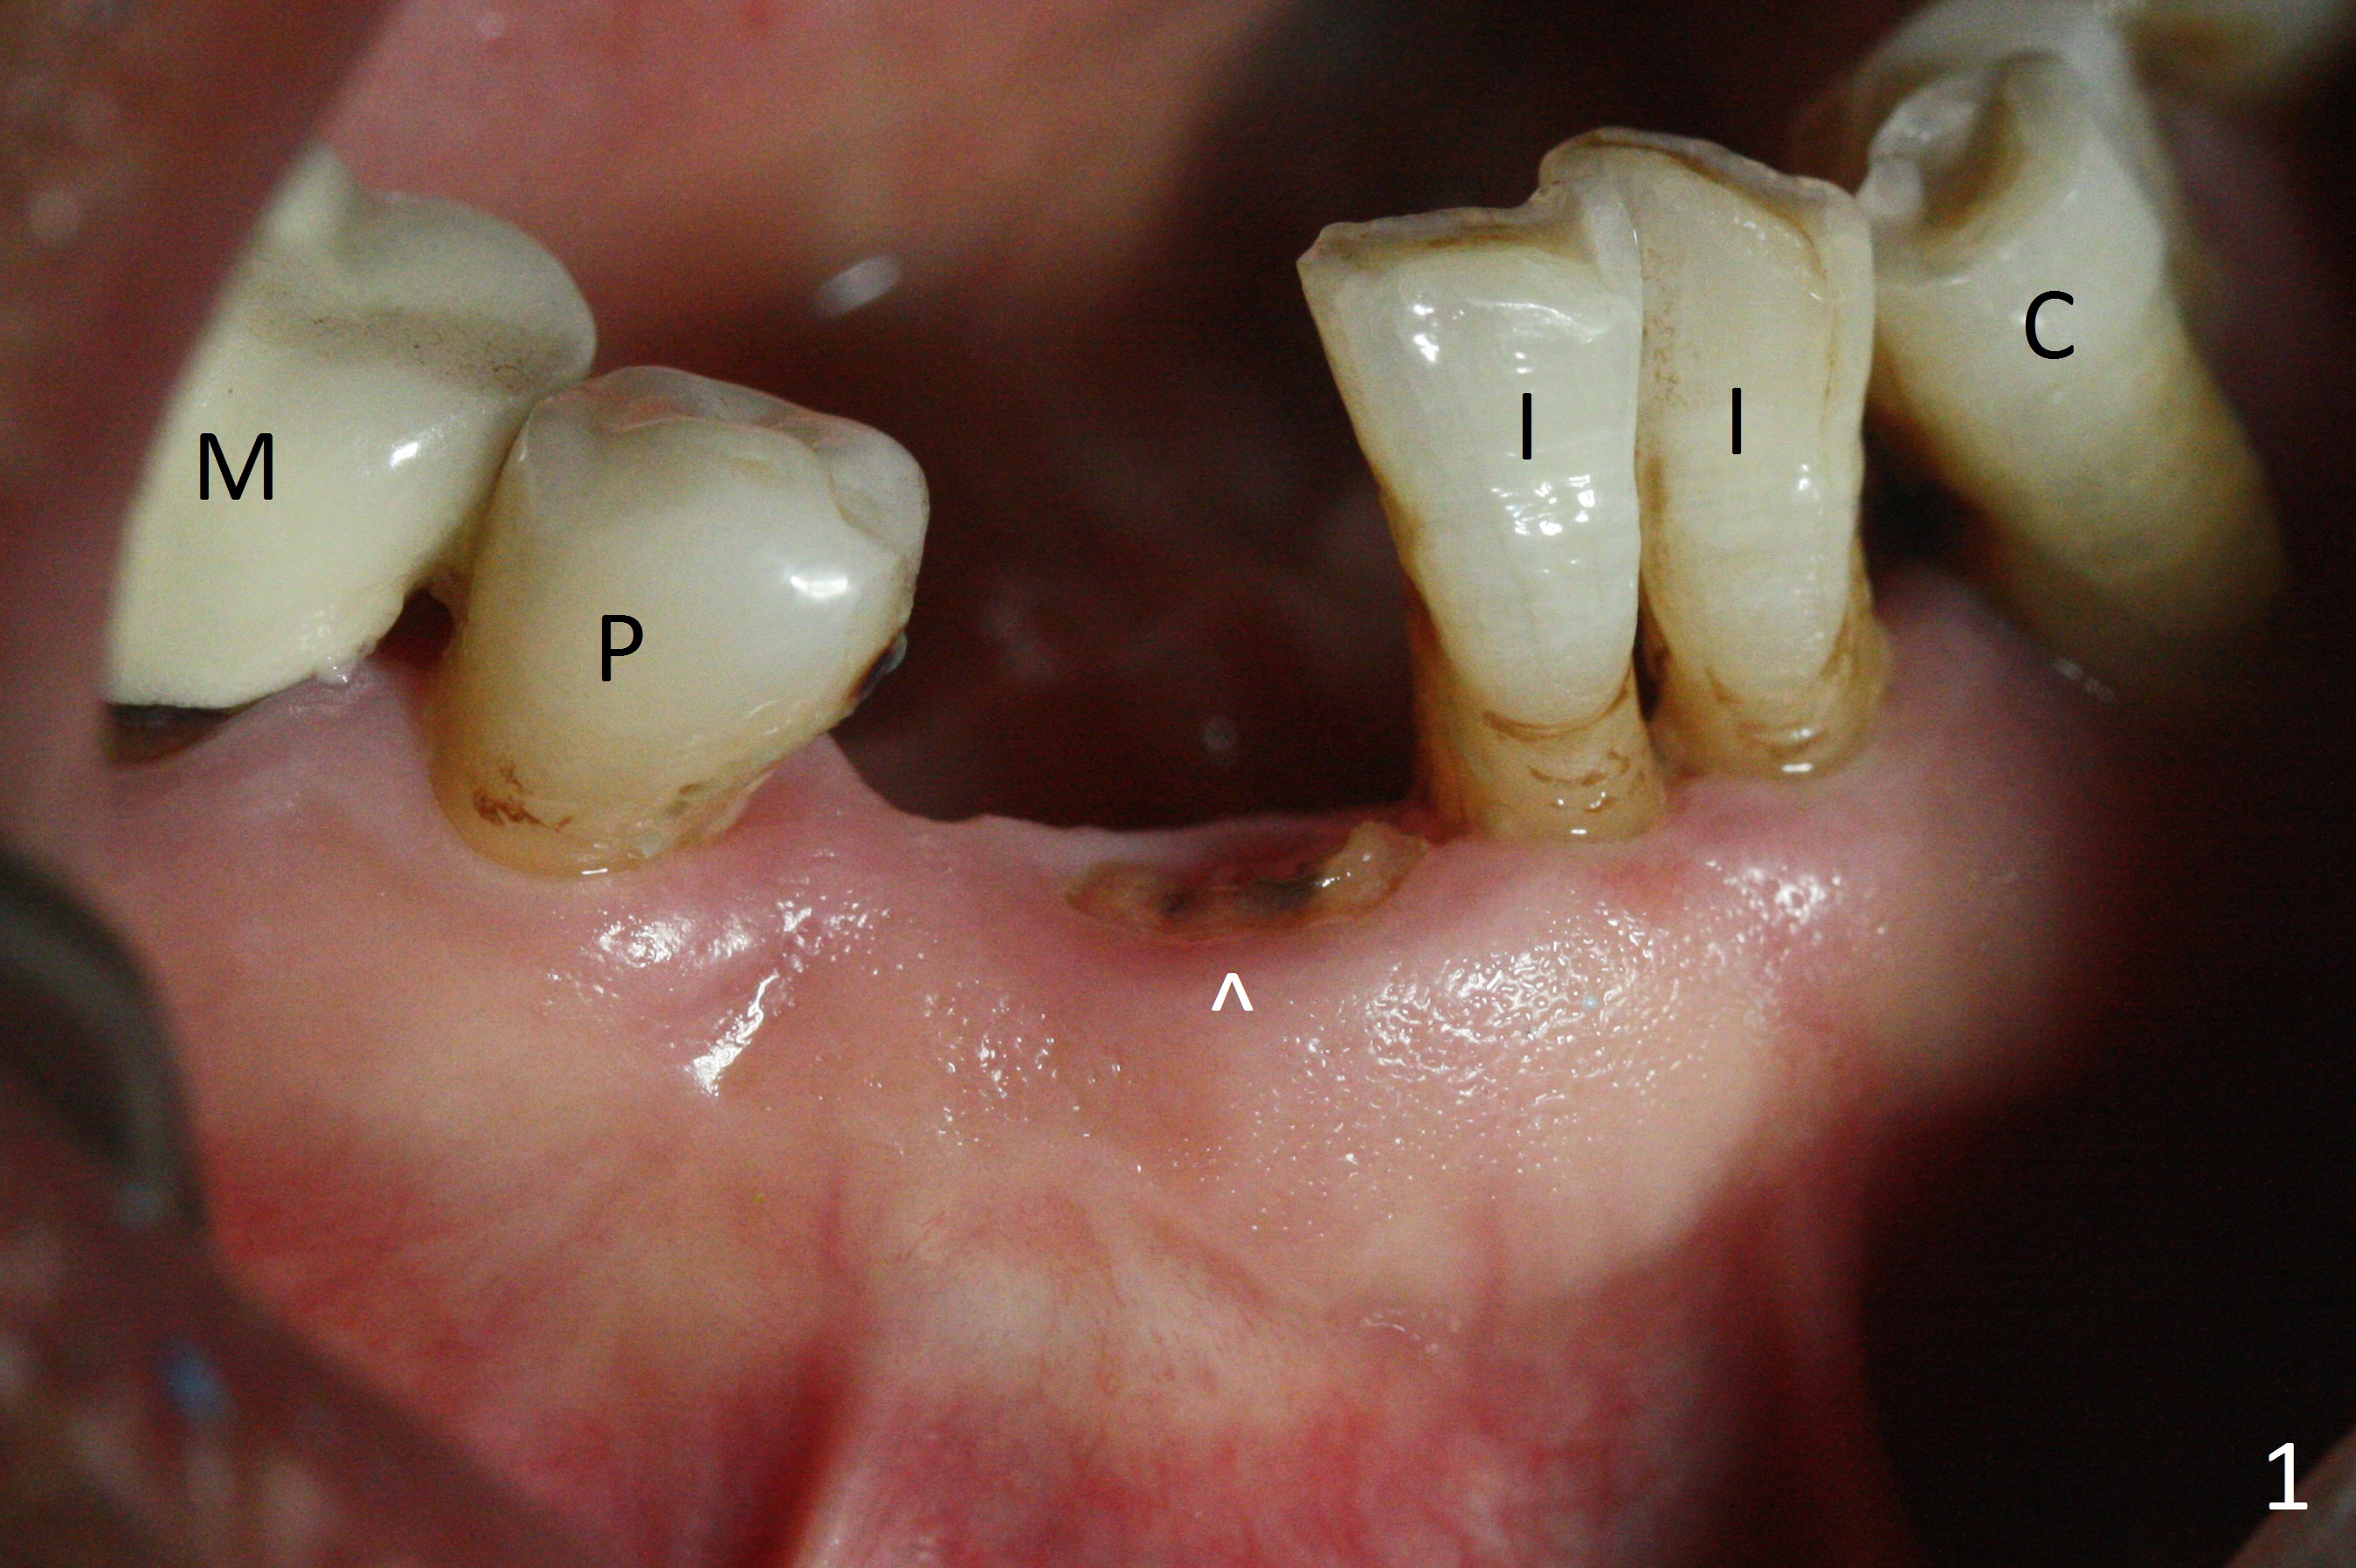

The lower dentition is special, consisting of a residual root (Fig.1 ^), 2 incisor (I), 1 canine (C), 1 premolar (P) and 1 molar (M). The residual root looks like an incisor with rotation of 90º (Fig.2,3). Osteotomy is initiated (Fig.4) for a 3x16(2) mm 1-piece implant (Fig.5 with 45 Ncm). The implant is being placed as distal as possible (Fig.4 arrow) so that a large canine-like provisional is to be fabricated in the large edentulous space (Fig.8,9) after bone graft (Fig.6,7 *). The gingiva around the provisional (Fig.10 P) remains healthy 11 days postop with occlusal clearance against the opposing dentition (Fig.11). The implant threads are not exposed with the help of bone graft 3 months 1 week postop (Fig.12). The gingiva around the implant is healthy (Fig.13). Soft tissue socket is formed by the provisional (Fig.14 *).